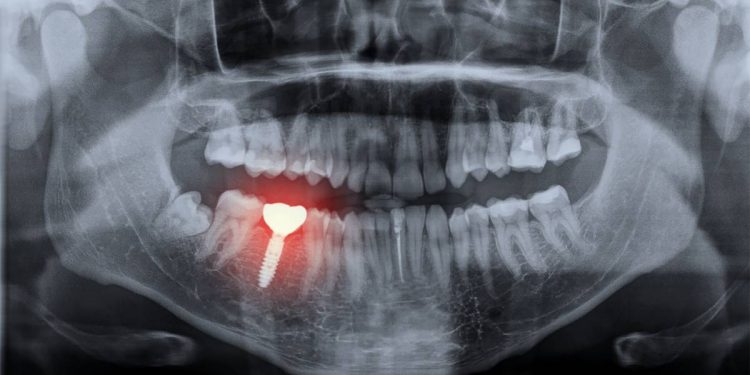

L’utilisation de la 3D dans la chirurgie dentaire augmente l’efficacité du professionnel. Celui-ci est désormais capable d’offrir des prestations avec une excellente précision. Par exemple, le scanner dentaire du cone beam et la radiographie panoramique 3D offrent en général un diagnostic et un bilan assez exhaustifs.

La radiographie panoramique en 3D au moyen d’un cone beam offre par exemple au spécialiste l’accès à un éventail d’informations utiles à l’établissement de son plan chirurgical. Cela assure une simulation juste de son opération dentaire.